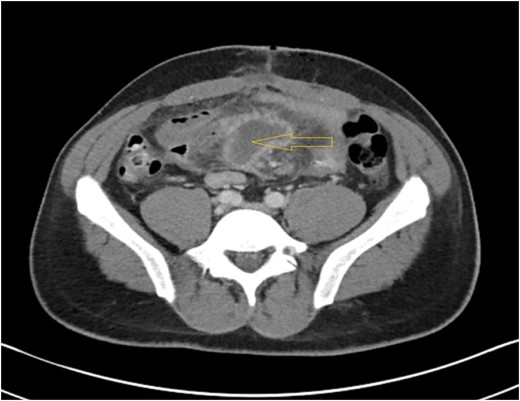

A 35-year-old HIV positive male on highly active antiretroviral therapy (HAART) presented to the Emergency room with progressive colicky abdominal pain for 7 days. Pain had gotten diffuse over this time with increased abdominal distension, nausea and bilious vomiting. Patient had no previous abdominal surgery or radiation. Laboratory results revealed a white blood cell count of 5.2 103 /μL, neutrophil 49.1%, hemoglobin 12.3 g/dL, hematocrit 39.4, platelet count of 247 103 /μL. Serum lactate, amylase and lipase levels were normal. X-ray of the abdomen demonstrated dilated small bowel loops within the mid-abdomen measuring approximately 4.5 cm in maximal transverse diameter, highly suggestive of partial small bowel obstruction. A double contrast CT scan of abdomen and pelvis (Fig. 1) showed partial small bowel obstruction with thickened loop of ileum and interloop abscess measuring 3.7 × 3.2 × 5.3 cm3 with diffuse mesenteric lymphadenopathy. Initial management consisted of NG tube suction, nil peros and intravenous (IV) fluid resuscitation. He received ciprofloxacin, metronidazole, vancomycin, sulfamethoxazole/trimethoprim (for pneumocystis jerovechi pneumonia prophylaxis), emtricitabine/tenofovir disoproxyl fumerate; darunavir; ritonavir and ethambutol. By hospital day four his condition did not improve with conservative management. At this time, decision was made to explore the abdomen. During the procedure, adhesiolysis and drainage of an 8 cm mid-ileal mesenteric abscess was performed (Fig. 2). Adhesive bands between the wall of the abscess and ileum compressing the underlying ileum were divided. The appendix appeared to be normal. Abscess materials were sent for microbiological cultures which grew MAC. A separate mesenteric lymph node biopsy was performed which showed reactive lymphadenopathy. Patient was discharged on postoperative Day 3 with oral antibiotics but he got readmitted the next day with complaints of abdominal pain, nausea and vomiting. A repeat CT scan of abdomen was performed which showed postoperative ileus, for which he was managed conservatively. He was discharged 2 days later with improvement of symptoms of nausea and vomiting. At 6 months follow up, he remained asymptomatic on HAART therapy with no evidence of gastrointestinal disturbance.